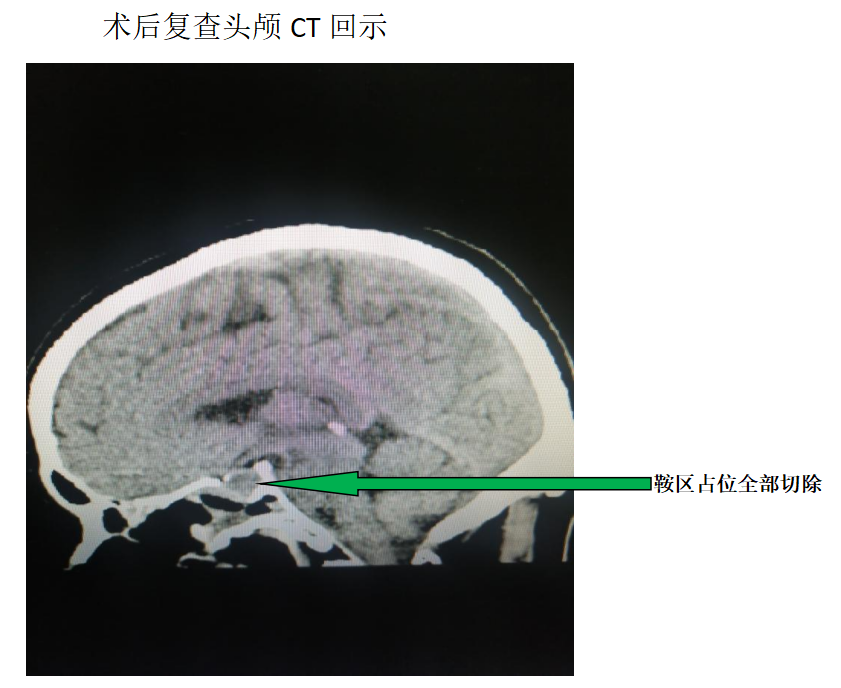

神经外科团队充分讨论后,一致认为孟先生手术指征明确,在全身麻醉下为他实施了经鼻蝶入路内镜下垂体瘤切除术。

经积极治疗后,孟先生未诉明显嗅觉及视力障碍,无脑脊液漏,顺利康复出院。